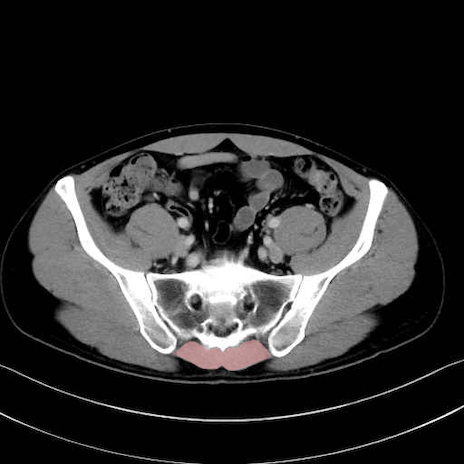

肛門挙筋 (Levator ani)